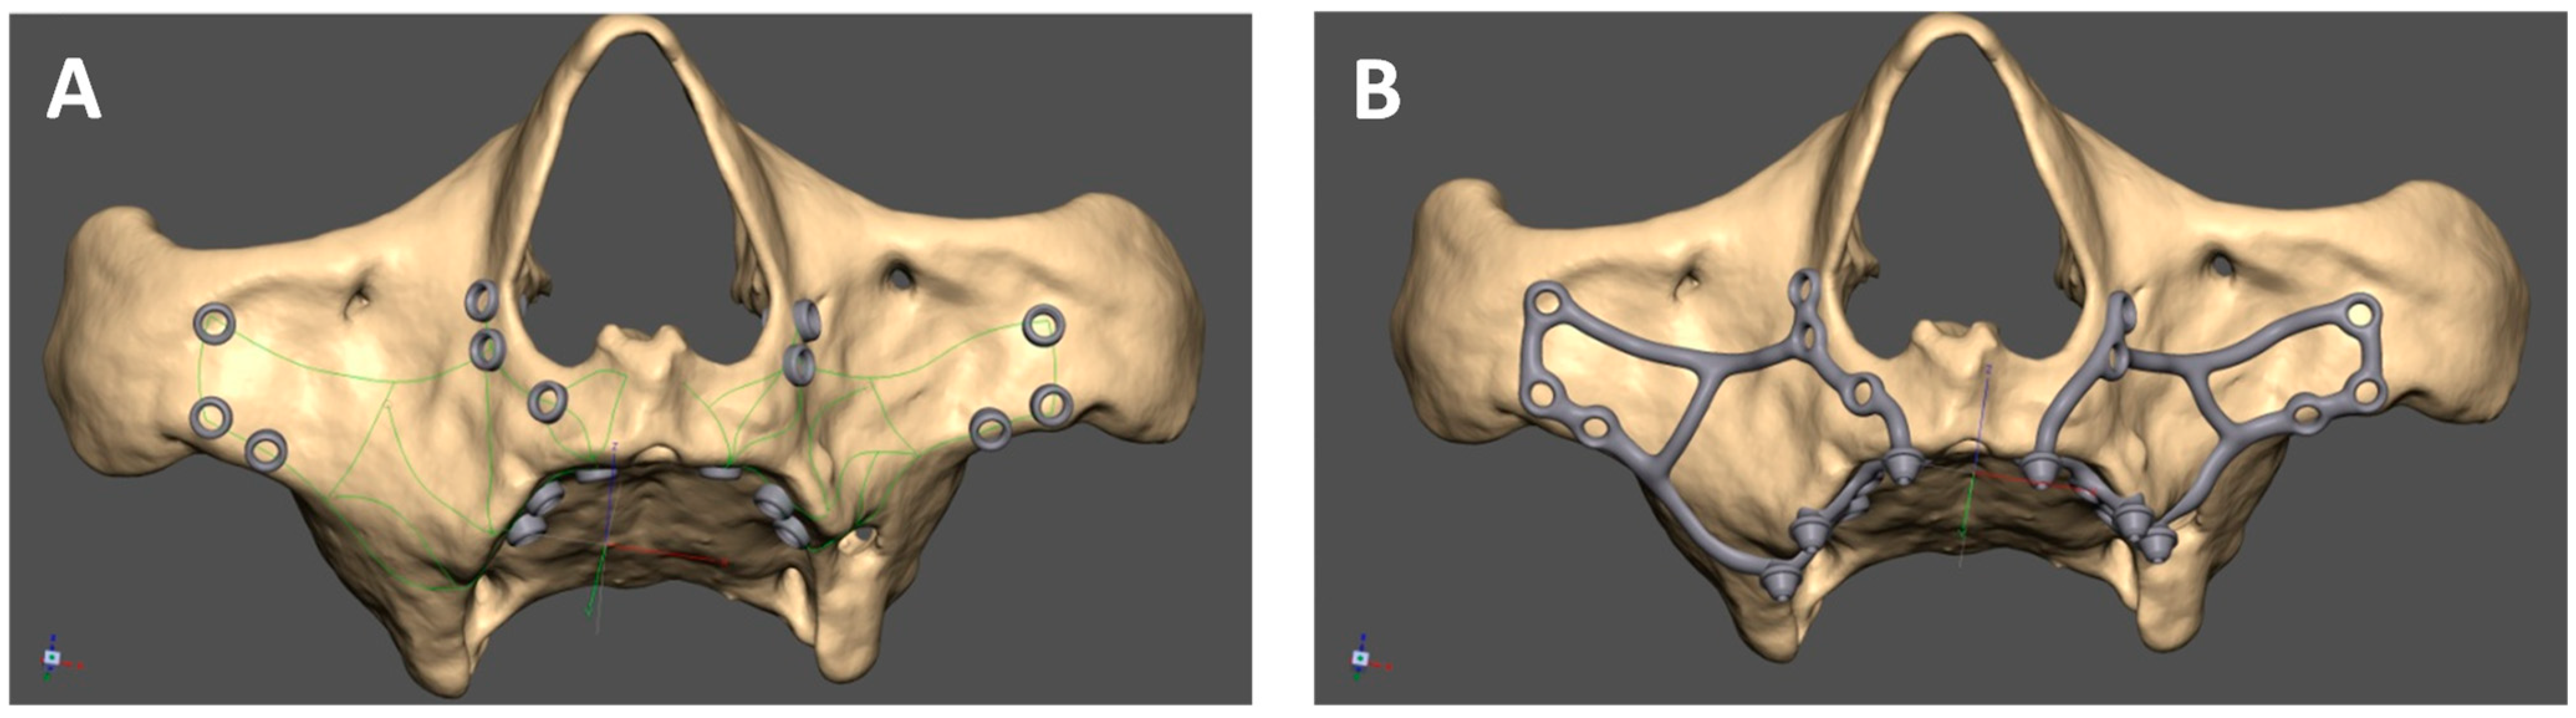

The manufacturing center gets in contact with the practitioner with a view to designing the Mai Implant®. The first thing the bioengineer does is import and analyze the bone model in an .STL file in Geomagic Freeform Plus®. Then, the implant mesh is designed in an .STL file. Holes for screws in areas where the bone is sufficiently thick are designed. After the modeling of implant meshes and placement of multiunits in appropriate positions, finishing, contouring, and adjustments of the implant to the bone are performed [Figure 4]. Then, an .STL file of the Mai Implants® is exported.

Figure 4. (A) Mai Implant® with holes where the bone is sufficiently thick. (B) Holes linked with connectors and the placement of multiunits in Mai Implant®.